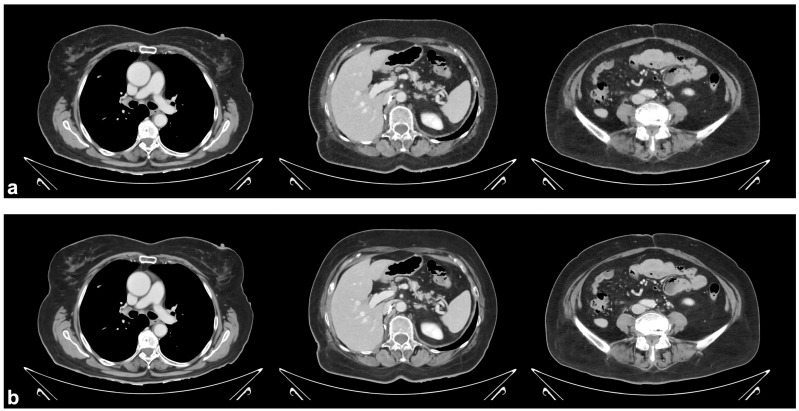

目的:本研究的目的是比较一种深度学习重建方法与现有的软组织CT图像重建方法的性能和鲁棒性。材料和方法:采用滤波后反投影、迭代模型重建(IMR)和深度学习重建(DLR),通过“标准”、“更清晰”和“更平滑”三个参数设置,对双层光谱检测器CT采集的门静脉期胸腹骨盆CT扫描(n = 99)进行图像生成。经验丰富的评分者通过考虑所有重建方法中十个代表性结构的衰减稳定性和图像噪声水平进行定量评估,并使用四点李克特量表(1 =差,2 =一般,3 =好,4 =优秀)对他们对“更平滑”的DLR和IMR图像的整体感知进行定性评估。一次扫描由于恶病质而被排除,这限制了定量测量。结果:定量测量的量表间信度为中等至优异(r = 0.63-0.96)。除腰大肌DLR与IMR的衰减值(平均+ 3.0 HU, p < 0.001)外,不同重建方法之间的衰减值无显著差异。图像噪声水平在所有结构的重建方法之间存在显著差异(均p < 0.001),并且在任何DLR参数设置下均低于FBP。“平滑”DLR的图像噪点水平主要低于或等于IMR,而“标准”DLR和“锐利”DLR的图像噪点水平则更高。“更平滑”的DLR图像在整体图像质量方面的平均评分高于IMR图像(3.7 vs. 2.3, p < 0.001)。结论:与FBP和IMR相比,经验丰富的读者认为“更平滑”的DLR图像质量更好,同时客观上也表现出更低或相当的噪声水平。

Objective: The objective of this study was to compare the performance and robustness of a deep learning reconstruction method against established alternatives for soft tissue CT image reconstruction. Materials and Methods: Images were generated from portal venous phase chest-abdomen-pelvis CT scans (n = 99) acquired on a dual-layer spectral detector CT using filtered back projection, iterative model reconstruction (IMR), and deep learning reconstruction (DLR) with three parameter settings, namely 'standard', 'sharper', and 'smoother'. Experienced raters performed a quantitative assessment by considering attenuation stability and image noise levels in ten representative structures across all reconstruction methods, as well as a qualitative assessment using a four-point Likert scale (1 = poor, 2 = fair, 3 = good, 4 = excellent) for their overall perception of 'smoother' DLR and IMR images. One scan was excluded due to cachexia, which limited the quantitative measurements. Results: The inter-rater reliability for quantitative measurements ranged from moderate to excellent (r = 0.63-0.96). Attenuation values did not differ significantly between reconstruction methods except for DLR against IMR in the psoas muscle (mean + 3.0 HU, p < 0.001). Image noise levels differed significantly between reconstruction methods for all structures (all p < 0.001) and were lower than FBP with any DLR parameter setting. Image noise levels with 'smoother' DLR were predominantly lower than or equal to IMR, while they were higher with 'standard' DLR and 'sharper' DLR. The 'smoother' DLR images received a higher mean rating for overall image quality than the IMR images (3.7 vs. 2.3, p < 0.001). Conclusions: 'Smoother' DLR images were perceived by experienced readers as having improved quality compared to FBP and IMR while also exhibiting objectively lower or equivalent noise levels.